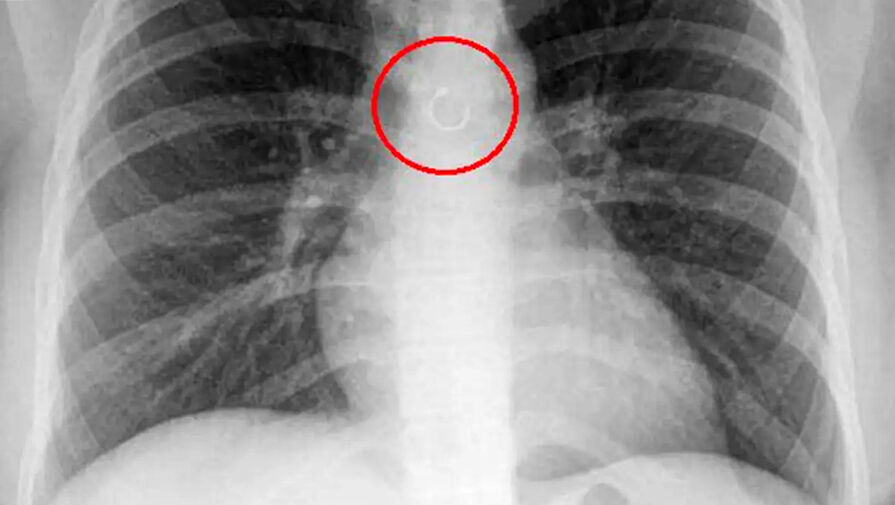

Женщина обнаружила, что потерянное кольцо в носу попало в ее легкие

Fox News: мексиканка случайно проглотила кольцо из носа, которое попало в легкие

В Мексике женщина обнаружила, что потерянное кольцо в носу попало в ее легкие, пишет Fox News.

Во время обследования выяснилось, что украшение из пирсинга в носу каким-то образом оказалось глубоко в дыхательных путях девушки и застряло в легких. Металлический элемент находился всего в полумиллиметре от аорты, что могло привести к опасным последствиям, добавили медики.